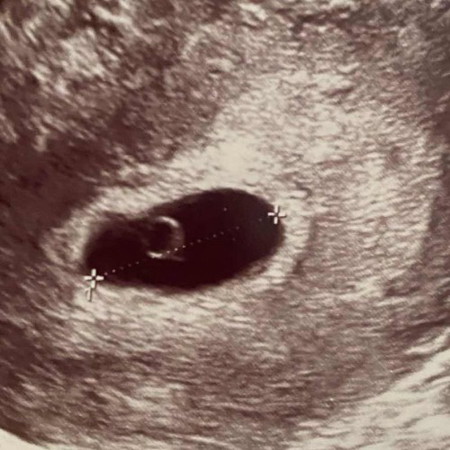

6w ถุงครรภ์และไข่แดงแบบนี้ปกติมั้ยคะ เป็นซีสในรังไข่5ซม.ด้วย กลัวจะหลุดหรือแค่ท้องลม หมอบอกทำอะไรไม่ได้เลยค่ะต้องรอดูเรื่อยๆ มีเปอร์เซ็นต์ที่น้องจะรอดมั้ยคะ แล้วบำรุงครรภ์ยังไงให้แข็งแรง